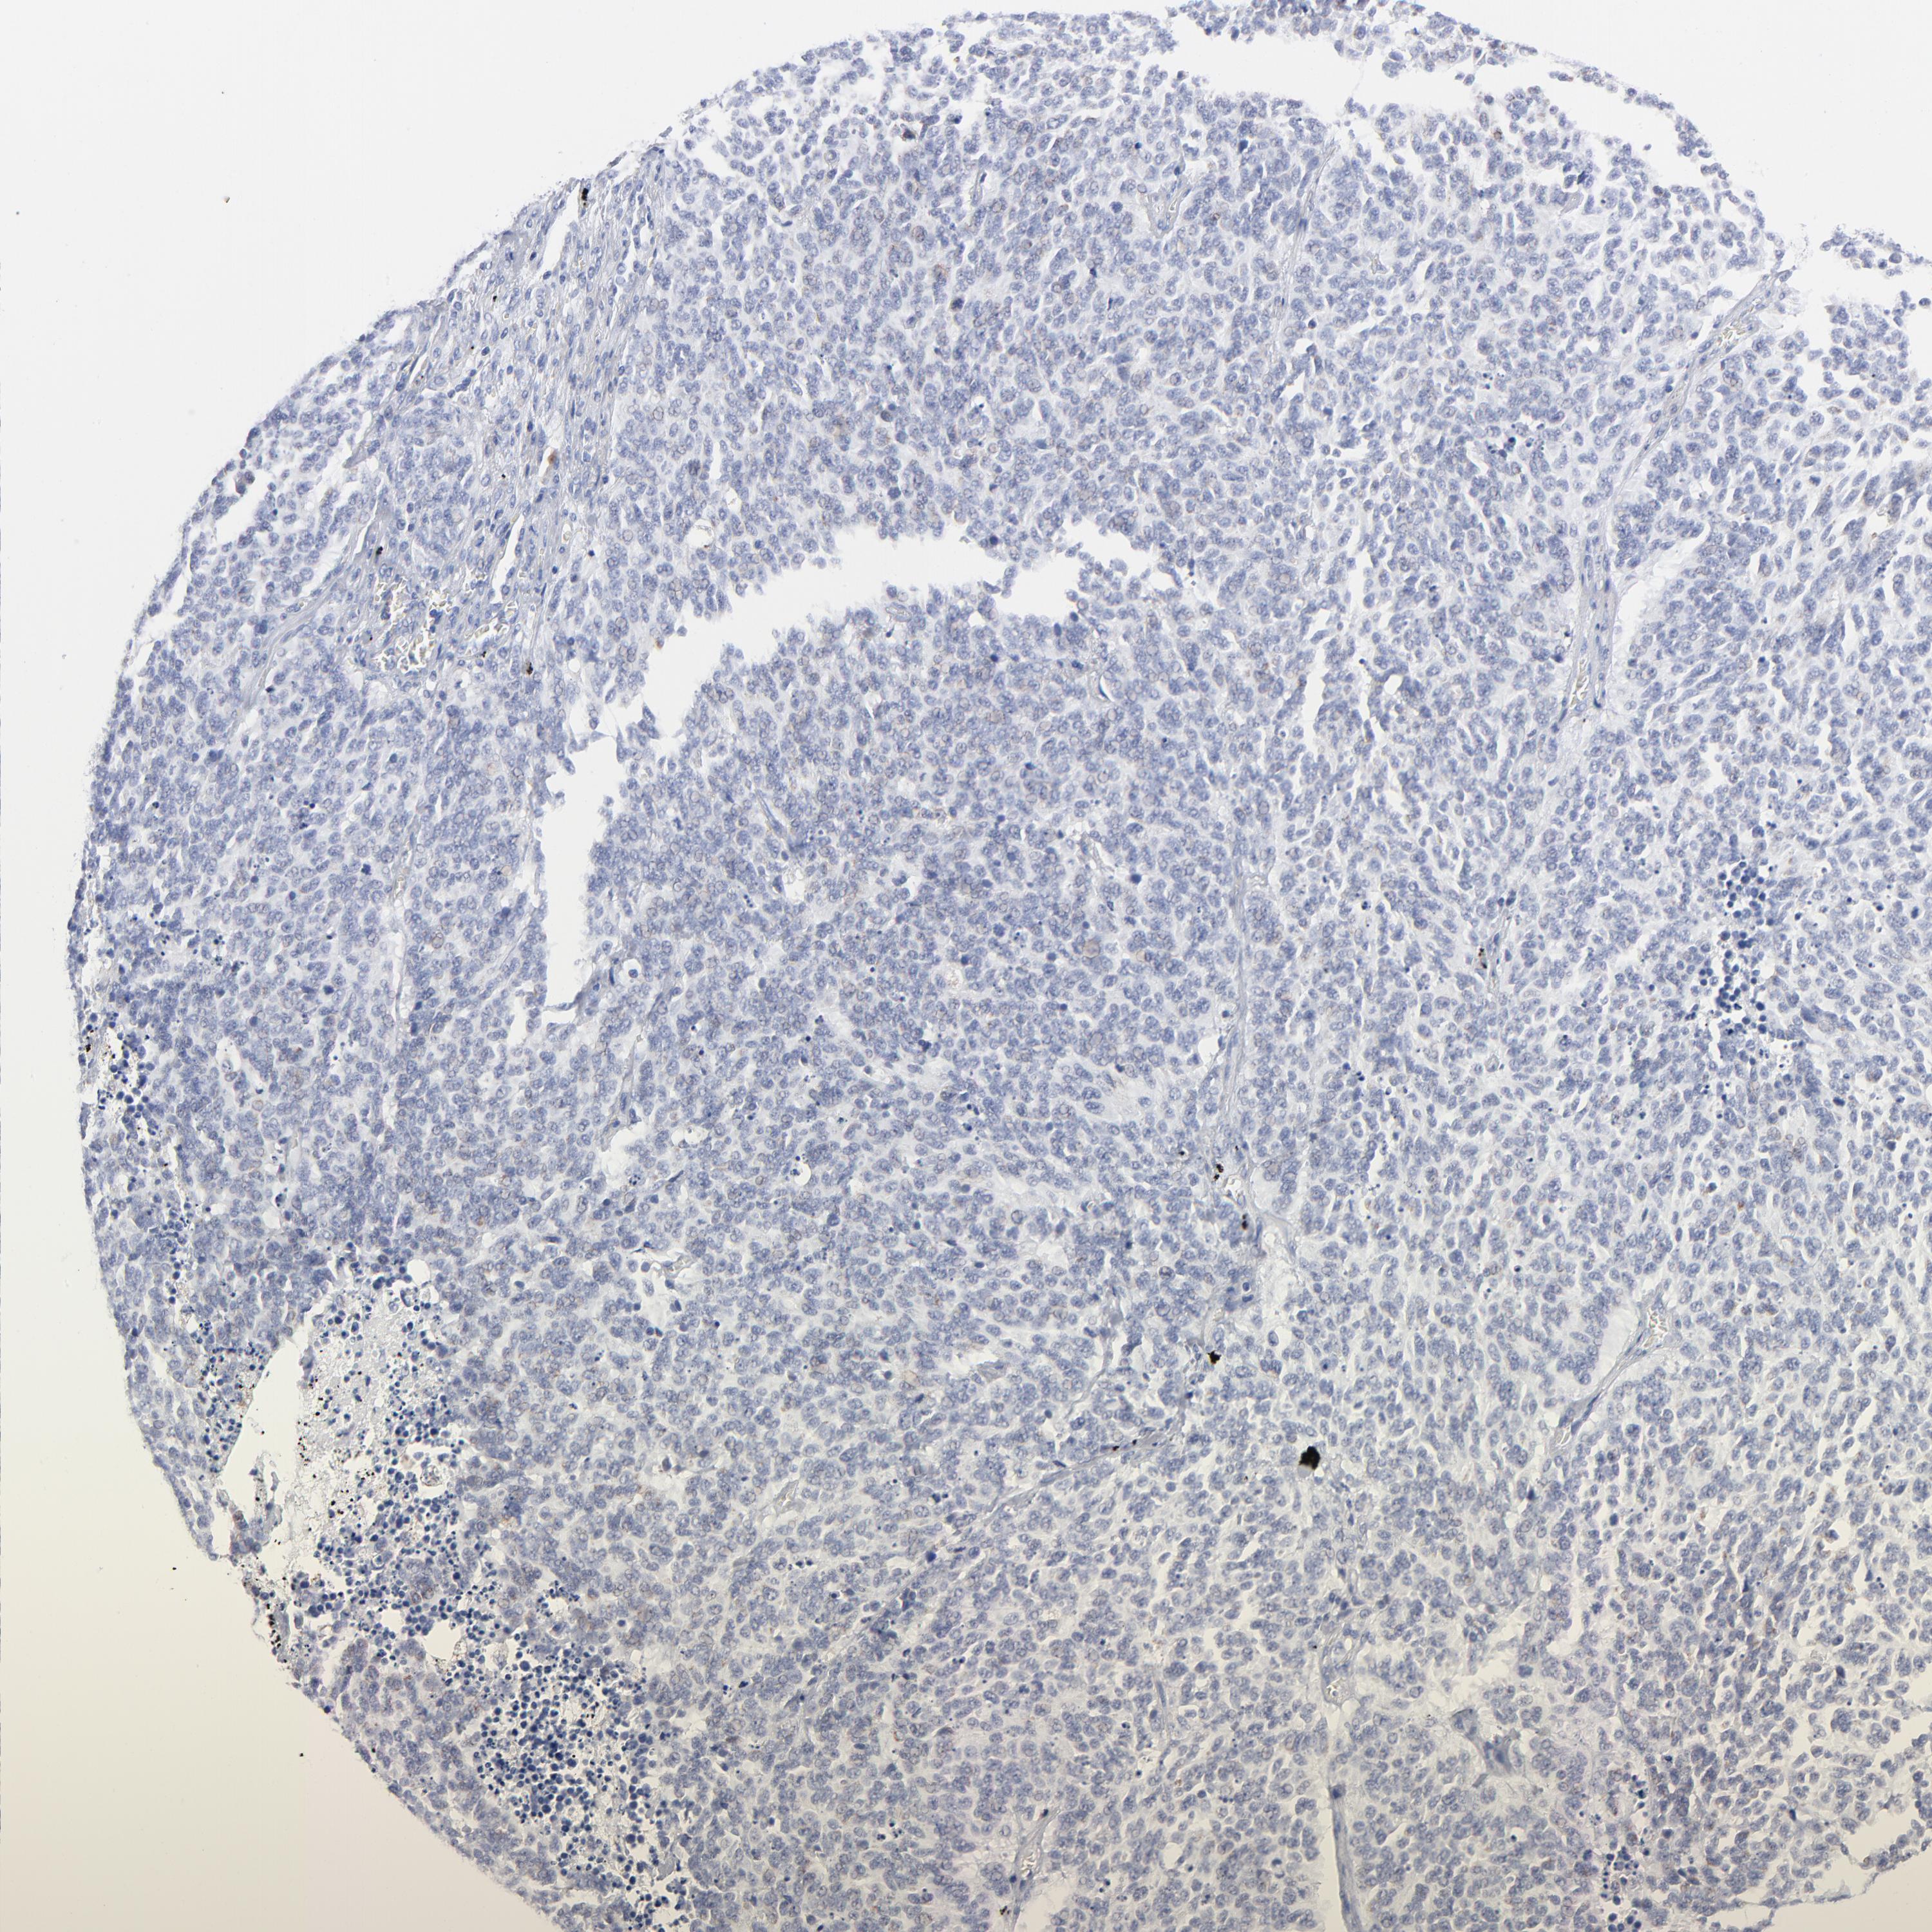

LUNG SQUAMOUS CELL CARCINOMA (TCGA) - Interactive survival scatter ploti

The Survival Scatter plot shows the clinical status (i.e. dead or alive) for all individuals in the patient cohort, based on the same data that underlies the corresponding Kaplan-Meier plots. Patients that are alive at last time for follow-up are shown in blue and patients who have died during the study are shown in red.

The x-axis shows the expression levels (FPKM) of the investigated gene in the tumor tissue at the time of diagnosis. The y-axis shows the follow-up time after diagnosis (years). Both axes are complimented with kernel density curves demonstrating the data density over the axes. The top density plot shows the expression levels (FPKM) distribution among dead (red) and alive patients (blue). The right density plot shows the data density of the survived years of dead patients with high and low expression levels respectively, stratified using the cutoff indicated by the vertical dashed line through the Survival Scatter plot. This cutoff is automatically defined based on the FPKM cutoff that minimizes the p-score. The cutoff can be changed by dragging the vertical line or by entering a cutoff value in the square labeled "Current cut-off".

Under the Survival Scatter plot the p-score landscape (black curve; left axis) is shown together with dead median separation (red curve; right axis). Dead median separation is the difference in median mRNA expression between patients who have died with high and low expression, respectively. It is calculated as follows: median FPKM expression of dead patients with high expression - median FPKM expression of dead patients with low expression. This is intended to aid the user in visually exploring custom cutoffs and the associated p-scores and dead median separation.

Individual patient data is displayed and can be filtered by clicking on one or more of the category buttons on the top of the page. Categories describing expression level and patient information include: high, low, alive, dead, female, male and tumor stages. The scale of the x-axis can be toggled between linear and log-scale by clicking on the "x log" button. Mouse-over function shows TCGA ID, patient information and mRNA expression (FPKM) for each patient.

& Survival analysisi

Kaplan-Meier plots summarize results from analysis of correlation between mRNA expression level and patient survival. Patients were divided based on level of expression into one of the two groups "low" (under cut off) or "high" (over cut off). X-axis shows time for survival (years) and y-axis shows the probability of survival, where 1.0 corresponds to 100 percent.

CHCHD10 is not prognostic in Lung Squamous Cell Carcinoma (TCGA)

: 47.39

P scorei

N/A

Average pTPM 90.2

Number of samples 489